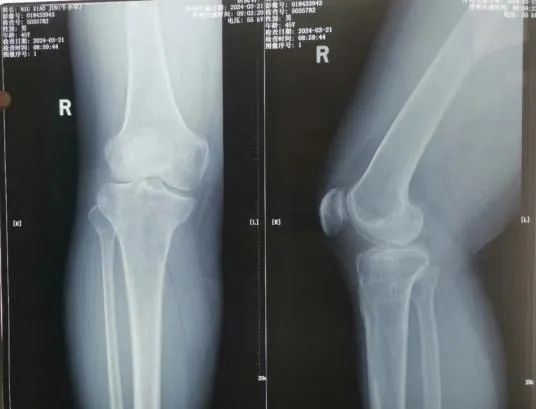

45岁的患者牛某,因5年前外伤致右胫骨平台骨折,未行手术治疗,伤后半年开始负重行走,致使右膝关节不稳定,且逐年加重。患者因右膝关节不稳定,不敢快速行走及下台阶,且摔倒数次,产生了恐惧心理。辗转多家医院后,均疗效不明显。 听闻“京长合作”首都医科大学附属北京积水潭医院每月定期派专家来长治二院骨科坐诊、查房、手术的医讯,主动要求北京积水潭专家手术治疗,近日来我院就诊要求住院手术治疗。 门诊经查体及阅读各项检查后以“右胫骨平台骨折畸形愈合”便收住院。 入院诊断: 1.右胫骨平台骨折畸形愈合 2.高血压病 住院期间,北京积水潭医院骨科吴宏华副主任医师结合查体及辅助检查,考虑患者畸形为关节外畸形,下肢力线向前内侧偏移,建议行胫骨内侧高位双平面截骨纠正对位及力线。考虑开放行双平面截骨,创伤较大,建议3D打印HTO截骨导板,在导报引导下行微创双平面截骨。在全身麻醉下在截骨导板引导下行截骨矫形术。 术后3天患者牛某持助行器下地行走,右膝关节不稳定感觉消失,恐惧心理消失,心情舒畅,对手术效果非常满意。 此次手术是在北京积水潭吴宏华副主任医师指导下,长治二院首次将HTO截骨技术应用于创伤骨科,是“京长合作”带给长治二院骨科发展的新动力,更为我市骨病患者带来的福音。 科室推荐 创伤骨科二病区隶属于长治二院骨科创伤专业,成立于 1978年建院之初,至今已历时 40 余年。创伤二病区现有开放床位 35 张,共有医师 10名(含返聘医师),护士 9 名。其中主任医师 1名,副主任医师 1 名、主治医师 6名、住院医师 2 名。 病区主任:李黎明,主任医师、长治市工伤医疗鉴定专家、北医三院进修学员,擅长复杂骨折的手术修复,尤其在骨盆骨折、关节周围骨折的手术治疗方面技术精湛。 创伤二病区诊疗疾病范围:肩胛骨骨折、肩(胸)锁关节脱位、锁骨骨折、肱骨近段骨折、肱骨干骨折、肱骨髁骨折、尺骨鹰嘴(冠突)骨折、尺桡骨骨折、桡骨远端骨折、各类型骨盆骨折、髋臼骨折、股骨头骨折、股骨颈骨折、股骨粗隆间骨折、股骨干骨折、股骨髁骨折、髌骨骨折、胫骨平台骨折、胫腓骨骨折、各类型踝关节骨折(韧带损伤)、各类型开放(闭合)性软组织损伤、陈旧性骨折不愈合、骨感染(骨髓炎)、内固定周围骨折、骨折非手术治疗、骨折康复指导等。 咨询热线 0355—3126025 主任医师 创伤骨科二病区主任 擅长复杂四肢骨折、骨盆骨折,脊柱骨折、颈椎病、腰椎管狭窄等的诊治。在肢体复杂损伤、脊柱退变疾病方面有较多深入研究。多次在北京、太原等省内外三甲医院进修学习,具有丰富的理论知识。 【学术任职】 长治医学院副教授、长治市骨科专业委员会委员、长治市足踝外科委员会委员、长治市医疗专家库成员,长治市工伤、司法鉴定专家组成员。在国家级省级专业杂志发表论文学术论文10余篇,在专业学术领域积累了丰富的临床经验。 医生推荐 徐彦芳 副主任医师 骨科学硕士 北京大学国内访问学者 【专业特长】 【学术任职】 咨询热线 李黎明主任 13097569000 徐彦芳医生 15635598825 供 稿丨徐彦芳 编 辑丨卞 晨 审 核丨雷 赫